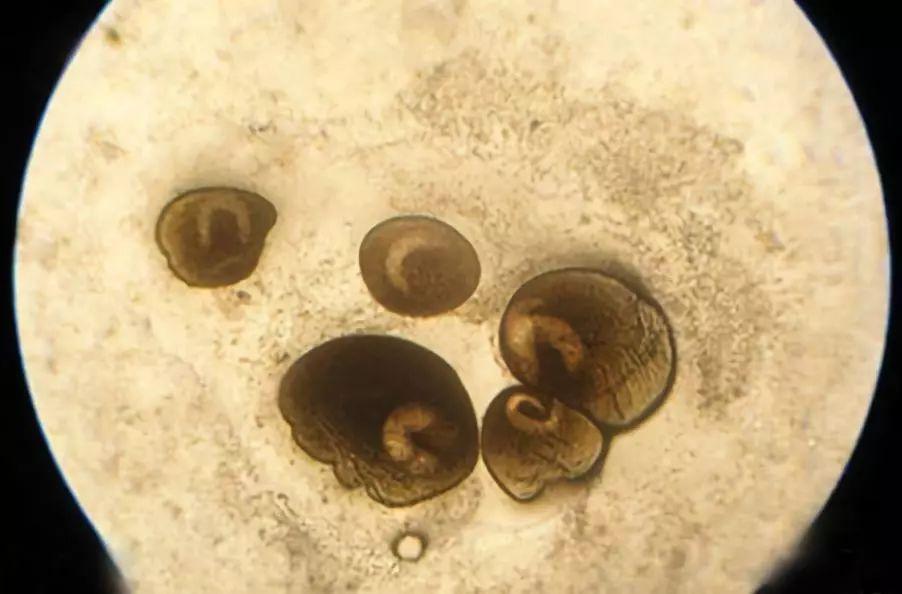

気温が高く過ごしやすい春の季節は猫がサナダムシ(瓜実条虫)に寄生(感染)されやすい時期でもあります。寄生の原因がノミと深い関係があり、私たち人にも寄生してしまう大変危ない寄生虫でもあります。サナダムシが寄生すると猫や私たちにはどのような影響があるのか、また駆除方法や.. この虫は、瓜実条虫(うりざねじょうちゅう:Dipylidium caninum)と呼ばれている寄生虫の片節です。. 瓜実条虫という名前の由来は、成虫の片節がキュウリ(胡瓜)の種(実)ような形をしていることによります。. 瓜の種のような片節が伸びたり縮んだりして.